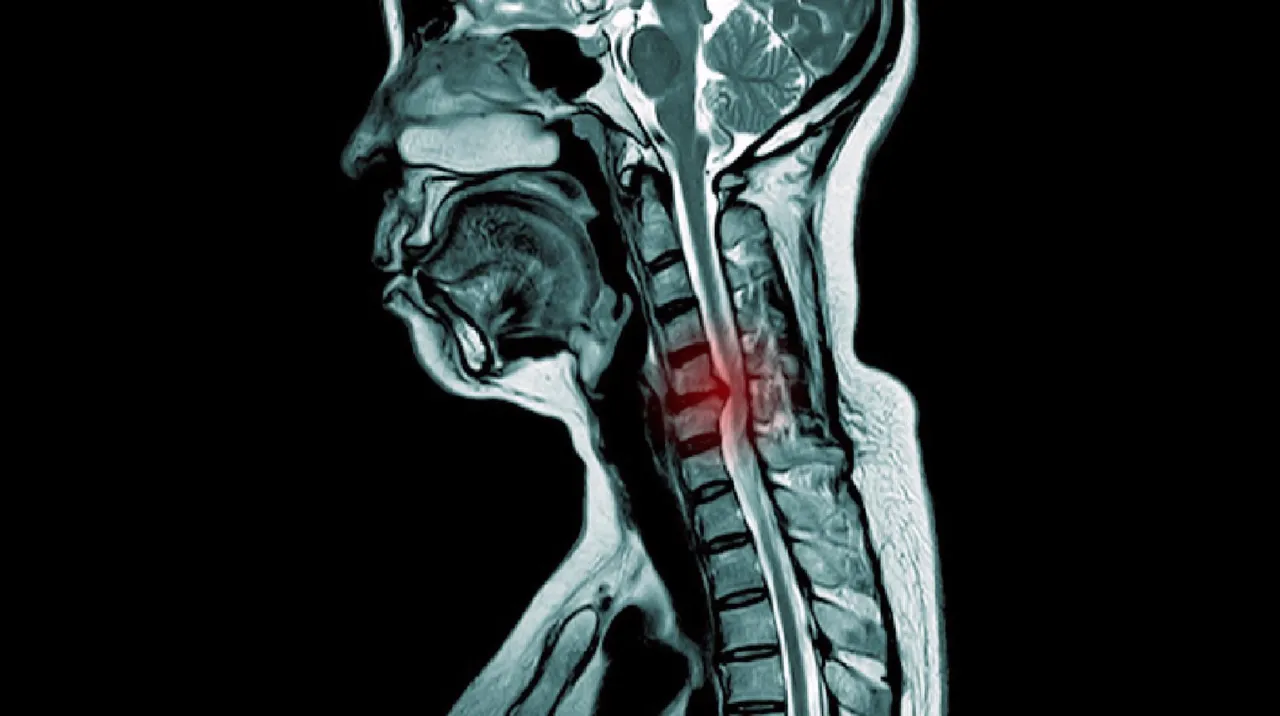

- Die Diagnose erfolgt durch neurologische Untersuchung und bildgebende Verfahren, primär die Magnetresonanztomographie (MRT).

Nach dem Gespräch folgt die neurologische Untersuchung. Hierbei prüft der Arzt Ihre Reflexe (z.B. den Bizepsreflex), testet die Sensibilität in verschiedenen Hautbereichen Ihrer Arme und Hände und beurteilt Ihre Muskelkraft. Dies gibt ihm wichtige Hinweise darauf, welche Nervenwurzeln betroffen sein könnten. Um den Verdacht auf einen Bandscheibenvorfall der HWS zu bestätigen und seine genaue Lage und Ausprägung zu beurteilen, ist die Magnetresonanztomographie (MRT) das Mittel der Wahl. Die MRT liefert detaillierte Bilder der Weichteile und kann den Bandscheibenvorfall und die Kompression der Nervenwurzeln klar sichtbar machen.